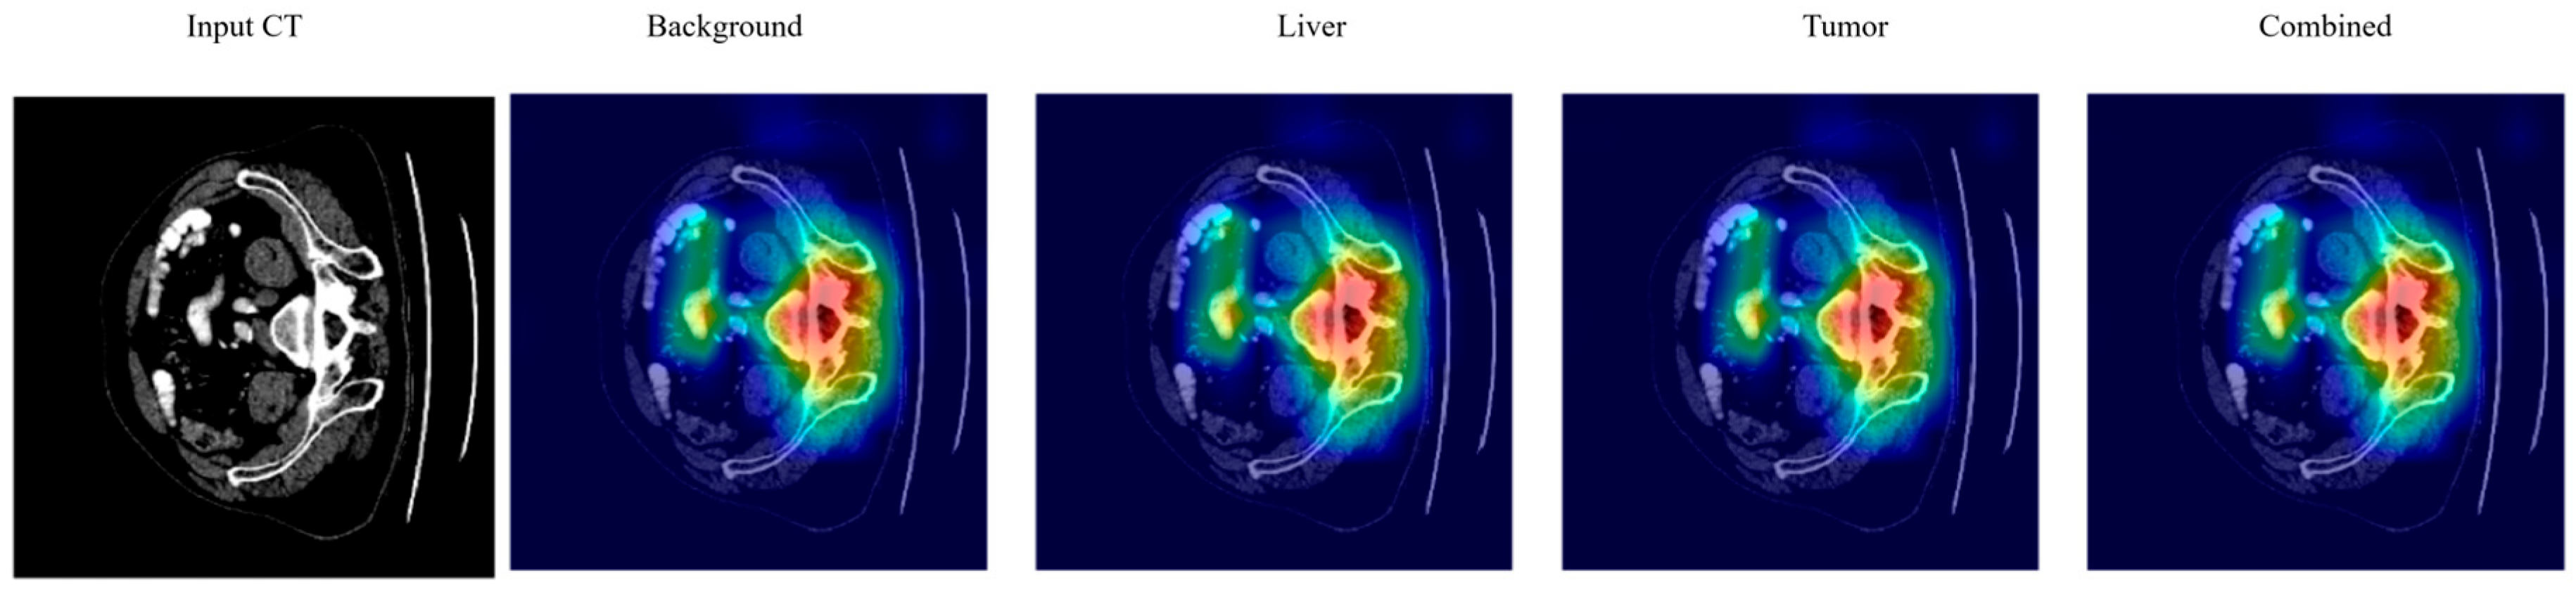

3.7. Explainable AI (XAI)

4.7. Explainable AI Analysis